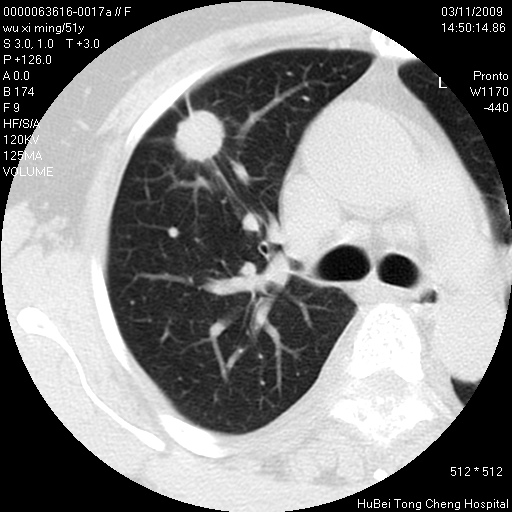

患者 女,51岁。因“胆囊炎,胆囊结石”,行常规术前胸部x线检查发现:右上肺结节病灶,建议行进一步检查。患者无咳嗽、咳痰及咯血等呼吸道症状,近期出现背部疼痛不适。

胸部ct轴位平扫(层厚10mm,螺距1.5,重建间隔10mm;部分层面:层厚3mm,螺距1.0,重建间隔3mm),图像如下:

1、周围型肺癌。(毛刺正、血管束集征,分叶。)

集束征,胸膜牽拉征,毛刺,淺分葉高度提示ca.

右肺周围型肺癌伴肺内转移及胸椎转移。已无手术机会。